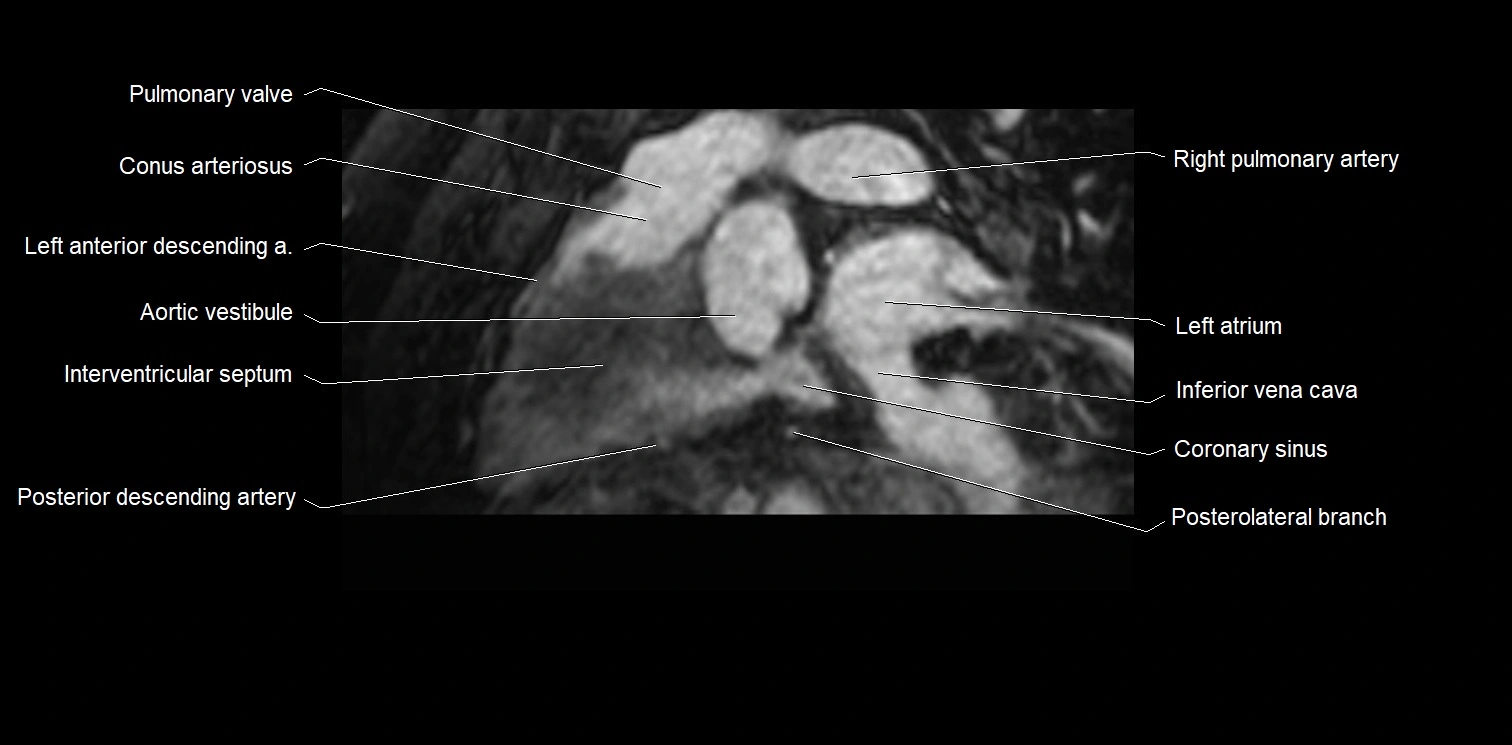

MRI image